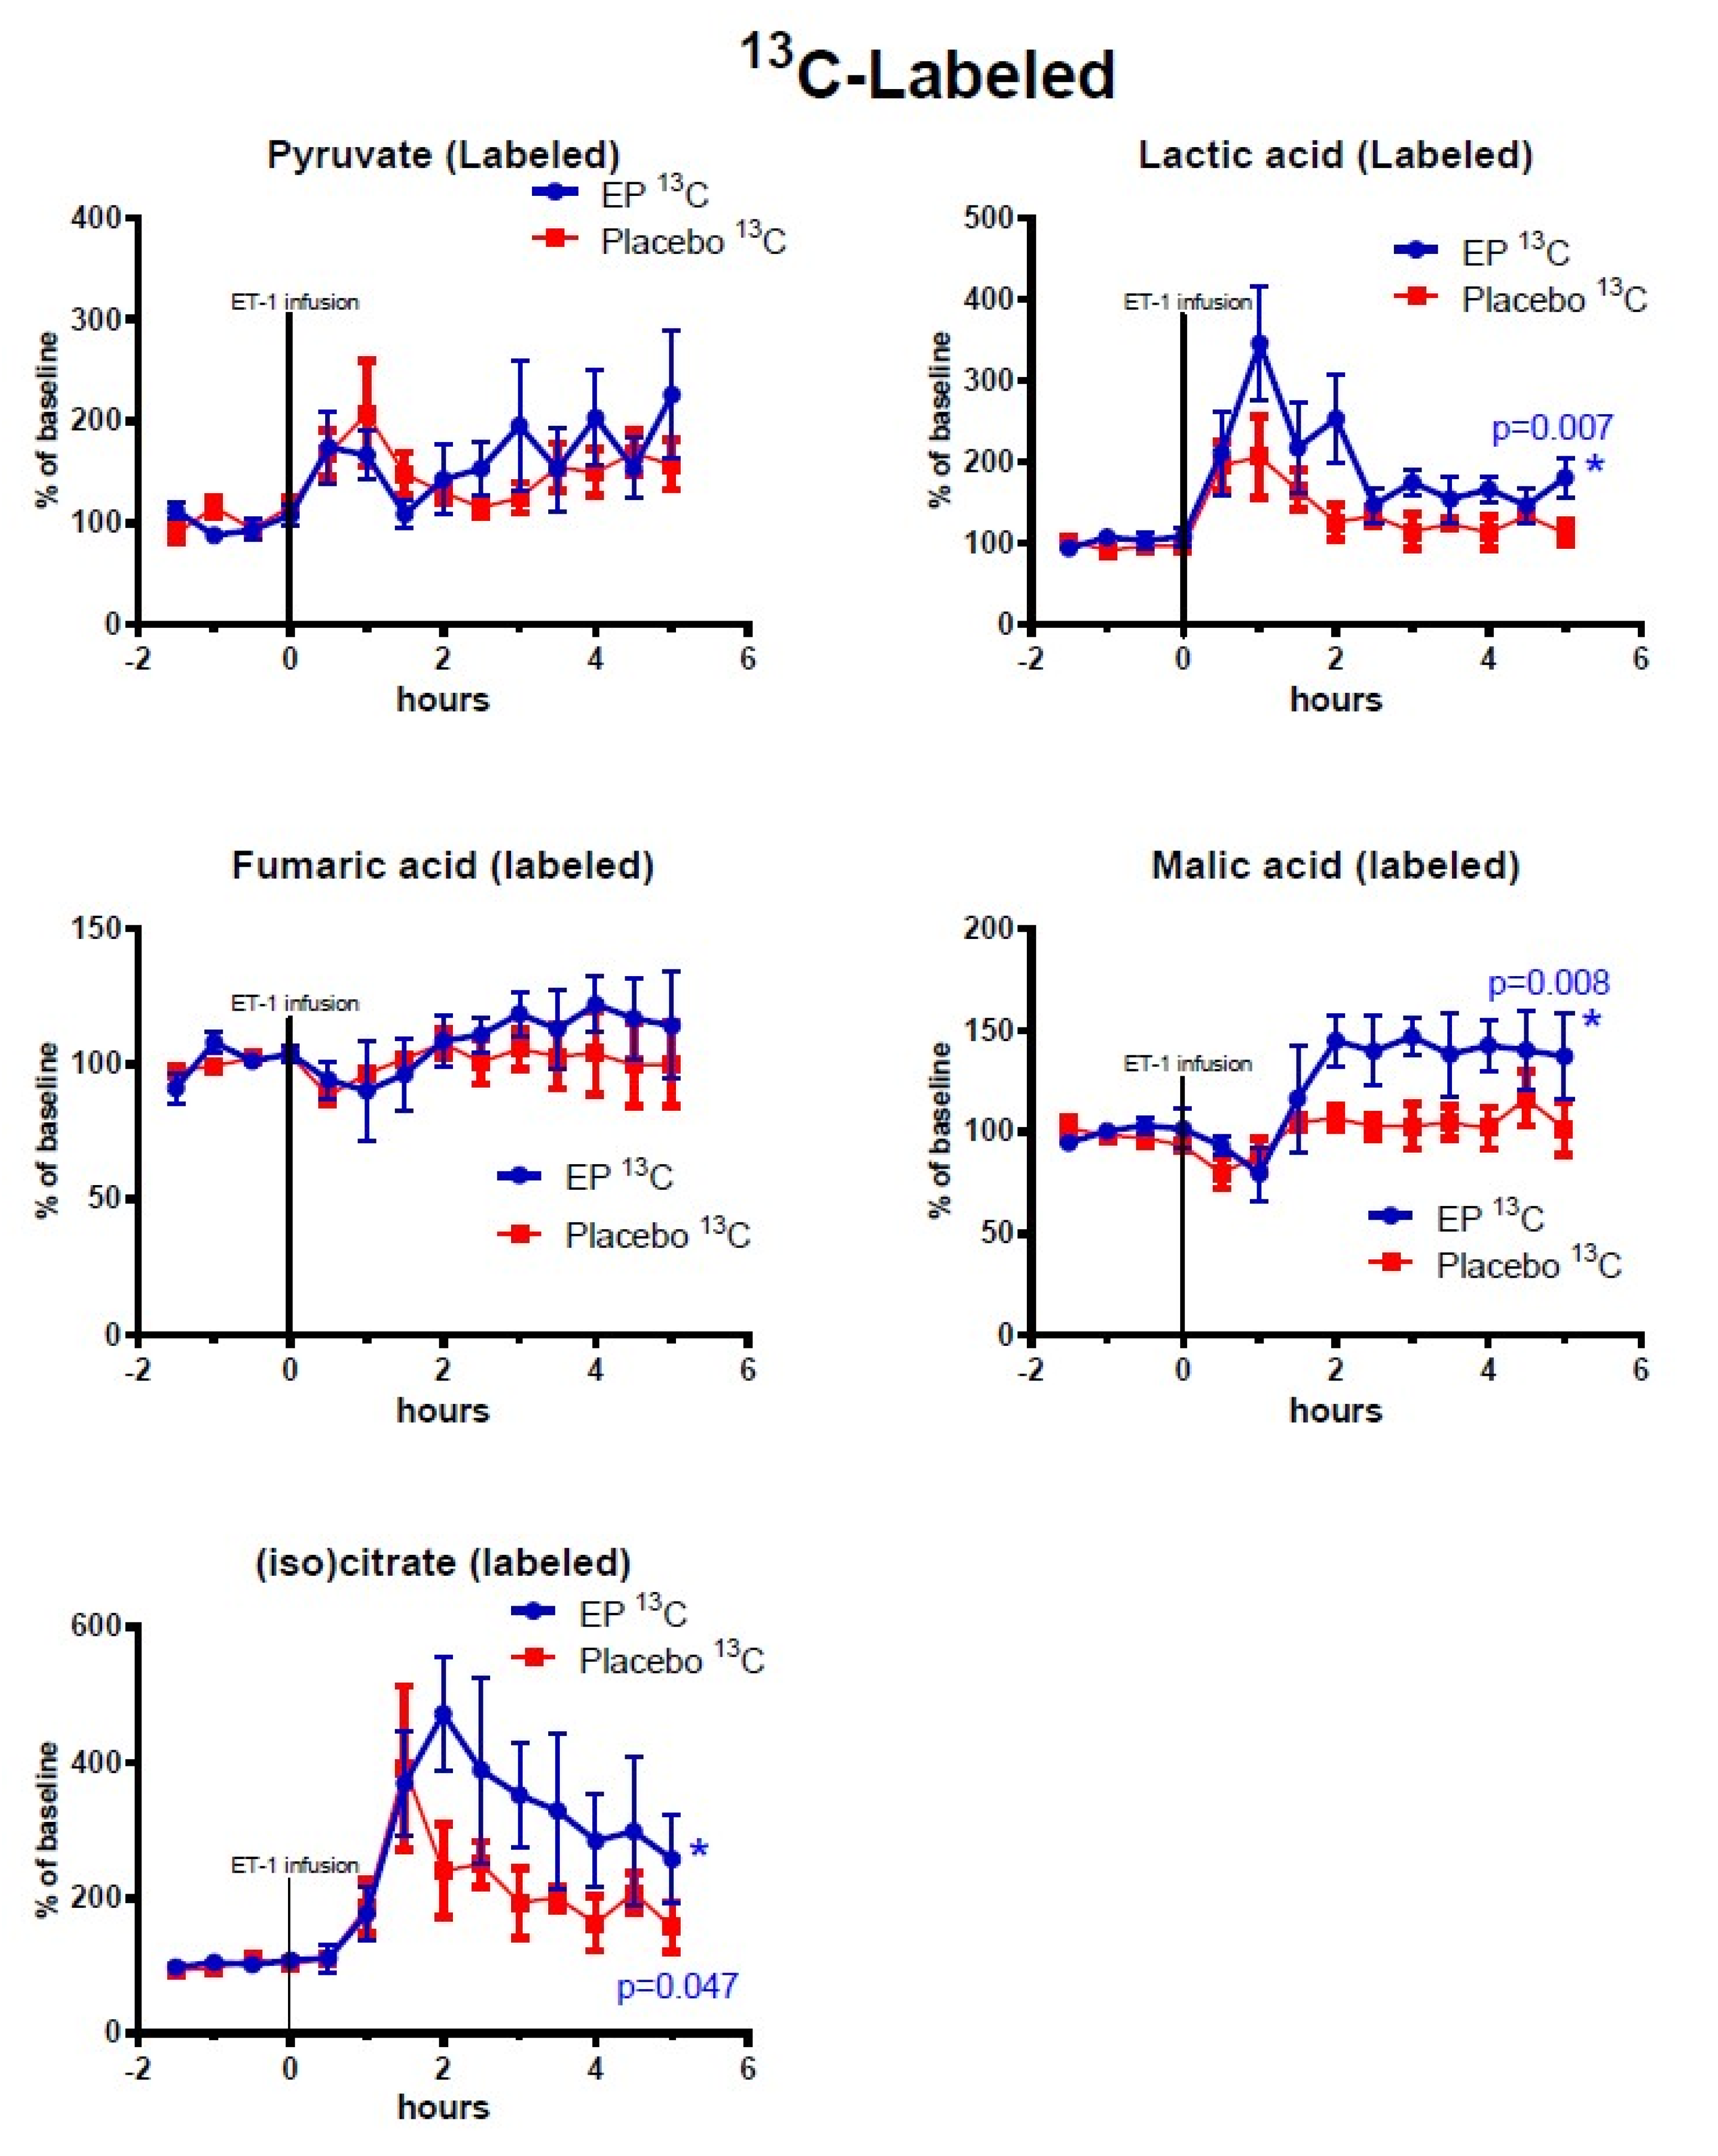

2. Results

2.2. Cerebral Microdialysis